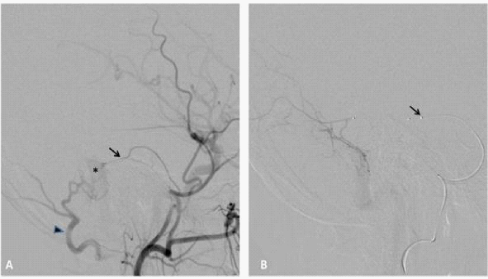

Figure 1 50year old man with left pulsatile tinnitus.

A. Digital subtraction angiography (DSA) of the of the left external carotid artery (ECA), lateral view, demonstrating a grade I IDAVF of the left lateral sinus supplied by the middle meningeal artery (black arrow) and occipital artery (black arrowhead). Note the early opacification of the lateral sinus (asterisk).

Super selective DSA, lateral view, the middle meningeal artery is accessed by a sonic 1.2F micro catheter black arrow.